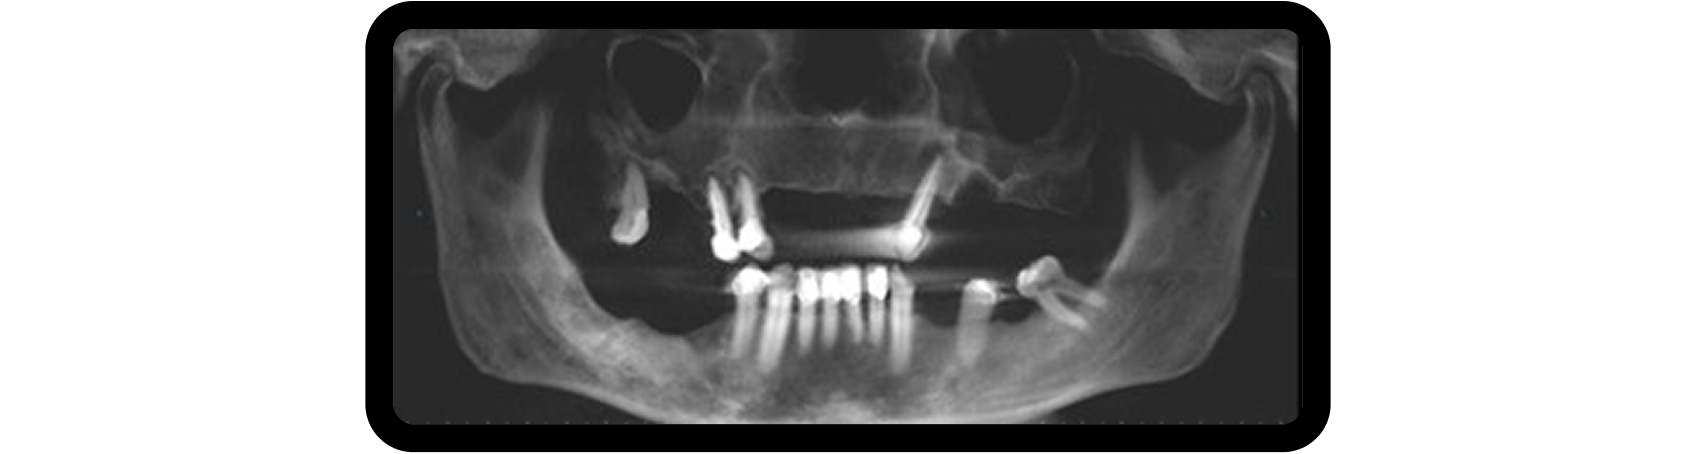

Bilateral sinus augmentation was required to support a six-implant, screw-retained zirconia restoration. A CBCT scan revealed radiolucencies in both maxillary sinuses, prompting referral to an ENT specialist before proceeding (Fig. 4).